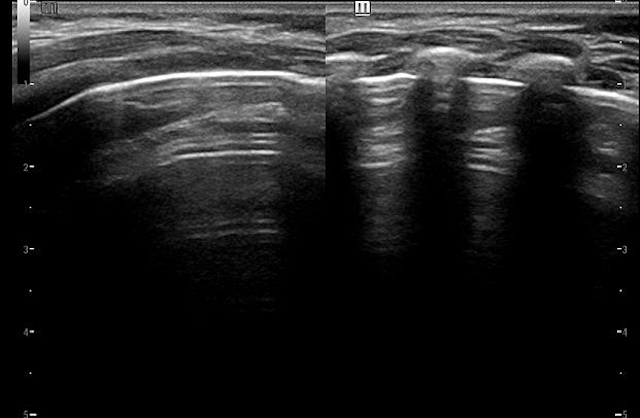

正常肺超声图